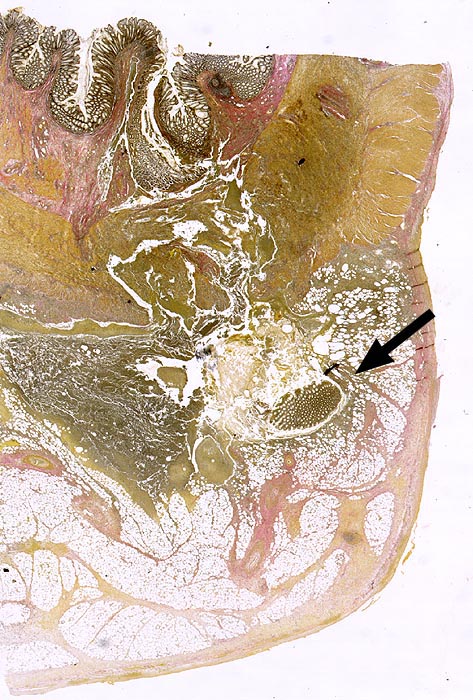

PathoPic ID 626 - Divertikulitis

Divertikulitis

Entzündung infektiös

Kolon Sigma

Darm, Anus

Partiell entzündlich zerstörtes Divertikel mit abszedierender Entzündung und

erhaltener Schleimhautinsel.

Histologie

Scan